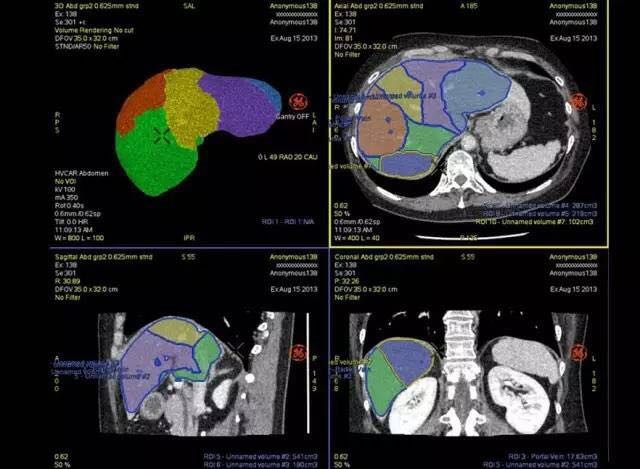

近日GE Revolution HD 精准能谱CT携手GE最新AW4.7后处理工作站在山东济南正式发布。和前款工作站相比,AW4.7功能更加强大,让圈内人不得不感叹GE在后处理软件技术的领先地位。 这台后处理站简直帅到没朋友: Hepatic VCAR 强大的VCAR系统,可见自动对肝脏进行分段,且对病灶及肝脏体积进行测量。外科医生一定非常喜欢这一功能。